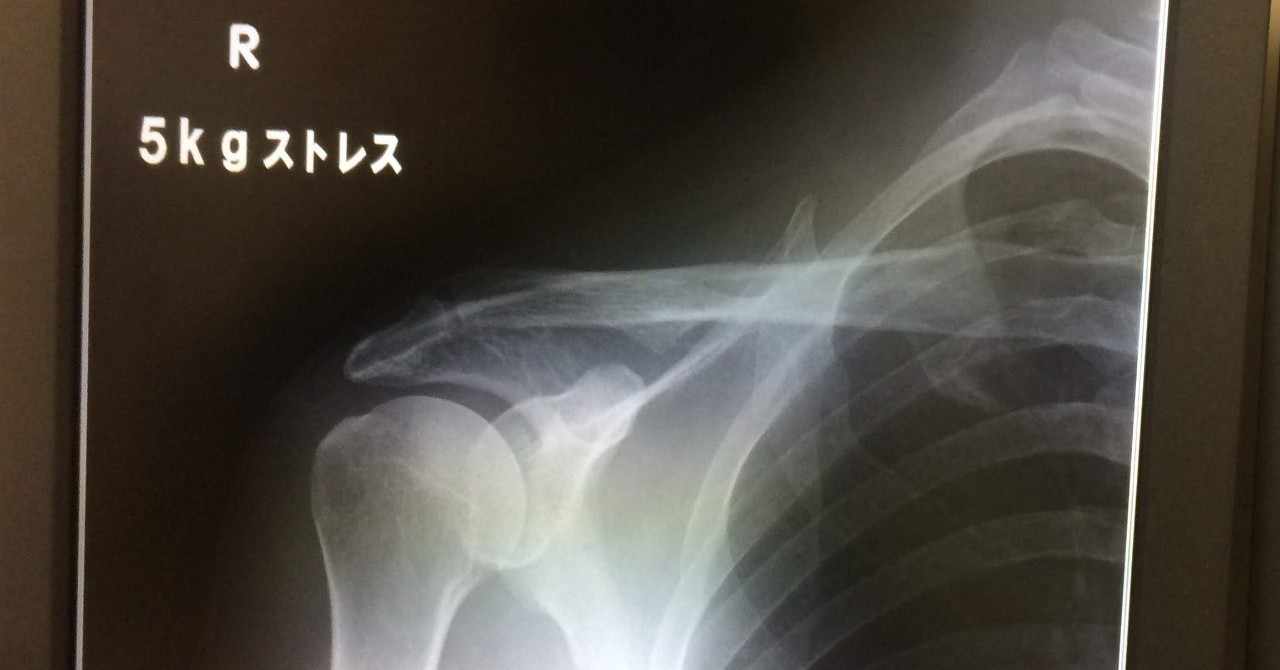

肩鎖関節脱臼 Strangemanどこへ行く